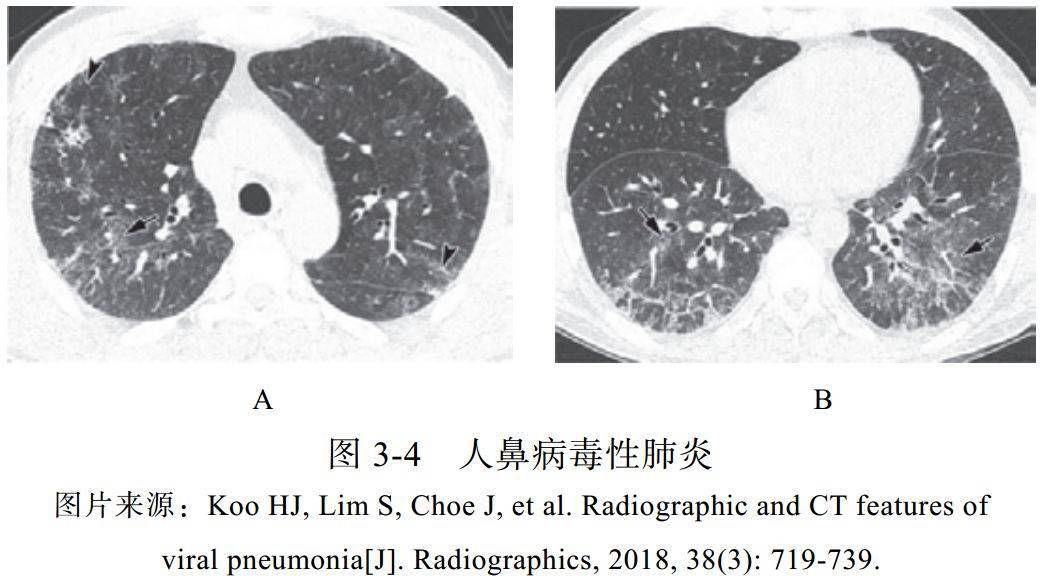

(四)人鼻病毒性肺炎

人鼻病毒(A、 B、 C)属于小 RNA 病毒科,是呼吸道感染的主要病原体,春季和秋季更常见,免疫功能低下的患者更容易感染,在需要入住 ICU 的重症肺炎患者中,人鼻病毒是最常见的病原体

病理机制为呼吸道上皮屏障破坏,导致血管通透性增加,黏液分泌增多

影像学表现:

(1)合并多灶性 GGO 和小叶间隔增厚(图 3-4)

(2)对于重型患者,可以观察到双侧斑片状实变影